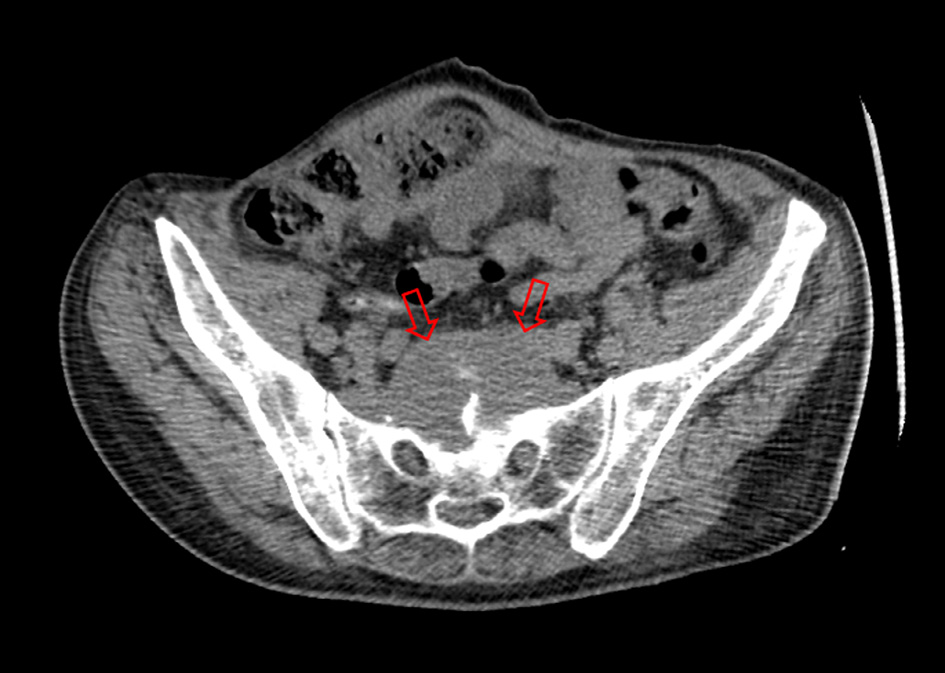

A 55-year-old patient with history of drug abuse was referred to our institution experiencing lower back pain and weakness in both lower extremities. It is also known, that patient has a long history of recurrent paravertebral abscesses previously treated with antibiotic therapy. This time pain was progressive, it increased on movements and reduced on rest. Clinical examination revealed tenderness on lower back palpation, weakness on both lower extremities and infected sacral bedsore. Computed tomography (CT) was performed, and L5/S1 vertebral space pyogenic spondylodiscitis was noticed along with left facet joint destruction and presacral abscess located in ventral sacral surface (Fig. 1).